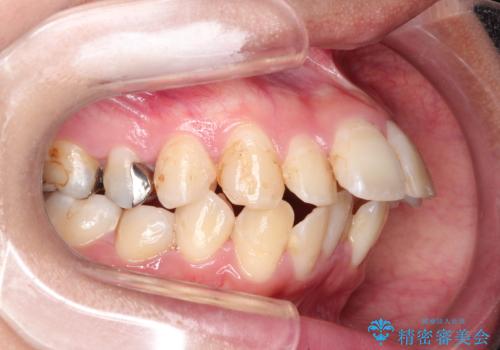

- 口元が出ていることを気にされて来院されました。精密な検査の結果、歯列全体のスペースが不足していることが判明。患者様のご希望である「口元を下げたい」というご要望を叶えるため、上下左右の小臼歯を抜歯し、そのスペースを利用して前歯を奥へ移動させる治療計画を立案しました。また、仕事上、目立つ矯正装置を避けたいというご希望から、上顎に裏側矯正、下顎に表側矯正を組み合わせたハーフリンガル矯正を提案しました。

今回の矯正治療では、口元を大きく下げるため、上下左右の小臼歯を抜歯しました。装置には、上顎は歯の裏側に装着する裏側矯正(舌側矯正)を、下顎は透明で目立ちにくい審美ブラケットを使用するハーフリンガル矯正を選択。これにより、治療中も他人の目を気にすることなく、ストレスなく過ごしていただけました。抜歯によってできたスペースを有効活用し、歯列全体を後方へ移動させることで、口元の突出感を解消。治療の結果、口元がすっきりと整い、自信のある美しい横顔を獲得していただけました。